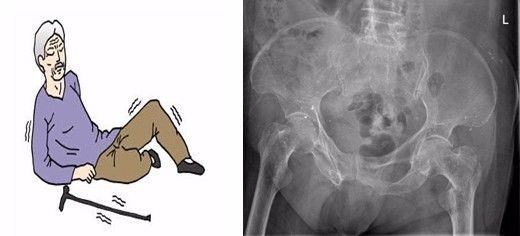

股骨粗隆间骨折,是指股骨大小粗隆间部位的骨折,也就是髋部骨折,是老年人最常见的骨折之一,常常导致患者死亡,故常被称为人生最后一次骨折。

一周前,江苏省中西医结合医院骨伤科迎来了一位特殊的老人,96岁高龄的钱奶奶,老人在家走路时不慎跌倒,髋部疼痛,不能行走,送至我院急,查髋部X线示:左股骨粗隆间粉碎性骨折,家里人一听很是紧张,赶紧住院治疗。

术后第三天查房,老奶奶伤口愈合很好,无红肿渗出,基本无疼痛,胃口很好,精神抖擞,嘴里不停的说着谢谢,复查X线:解剖复位。